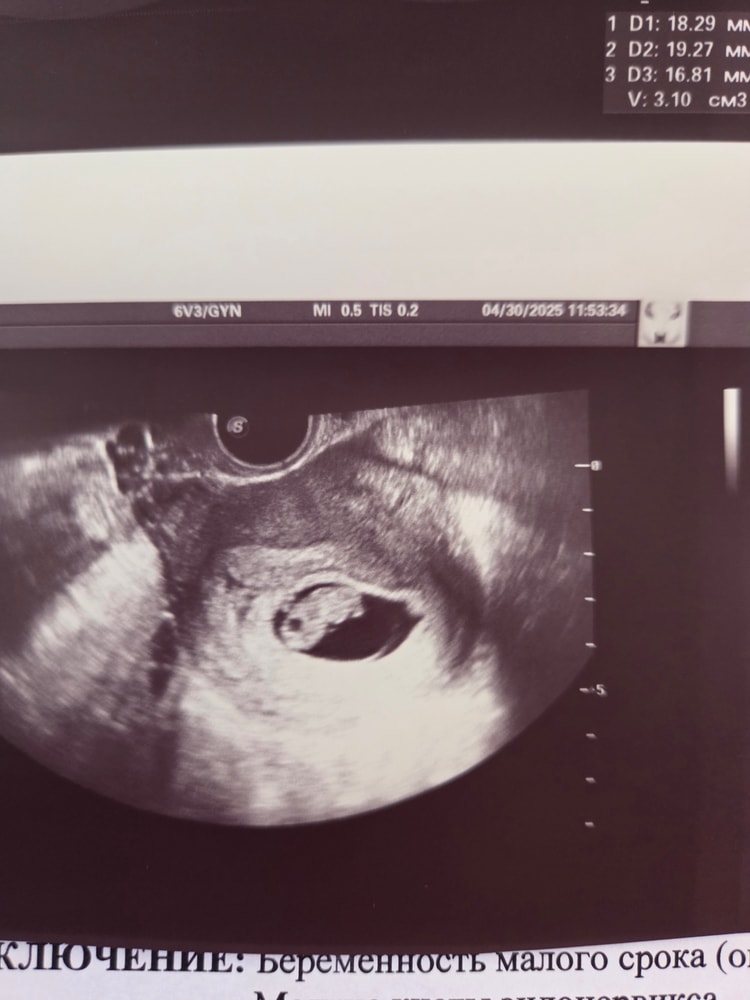

А вот 👇сегодняшнее узи 30.04, лечение помогло, гематомы нет совсем,ура)) Ни разу ничего не кровило и не болело. И еще была жидкость в позадиматочном пространстве на всех предыдущих узи 16,5 см3. Так мне никто из врачей и не ответил почему,и что с ней делать, но наконец на сегодняшнем узи ее почти нет, всего 3 см3 осталось 👍 Чуть беспокоит горечь во рту постоянная,но я уже даже привыкла ,вот такой у меня токс,хорошо хоть не рвет,только мутит иногда от мыслей и вида колбасы и яиц😃

Малыш уже подрос, сответствует сроку как раз 8+3. ПЯ 28×41×43, желточный 5,5 мм, ктр 17,9 мм, сб+. Ну такая сладкая фасолинка, расти и дальше хорошо, встретимся в начале декабря 🥰